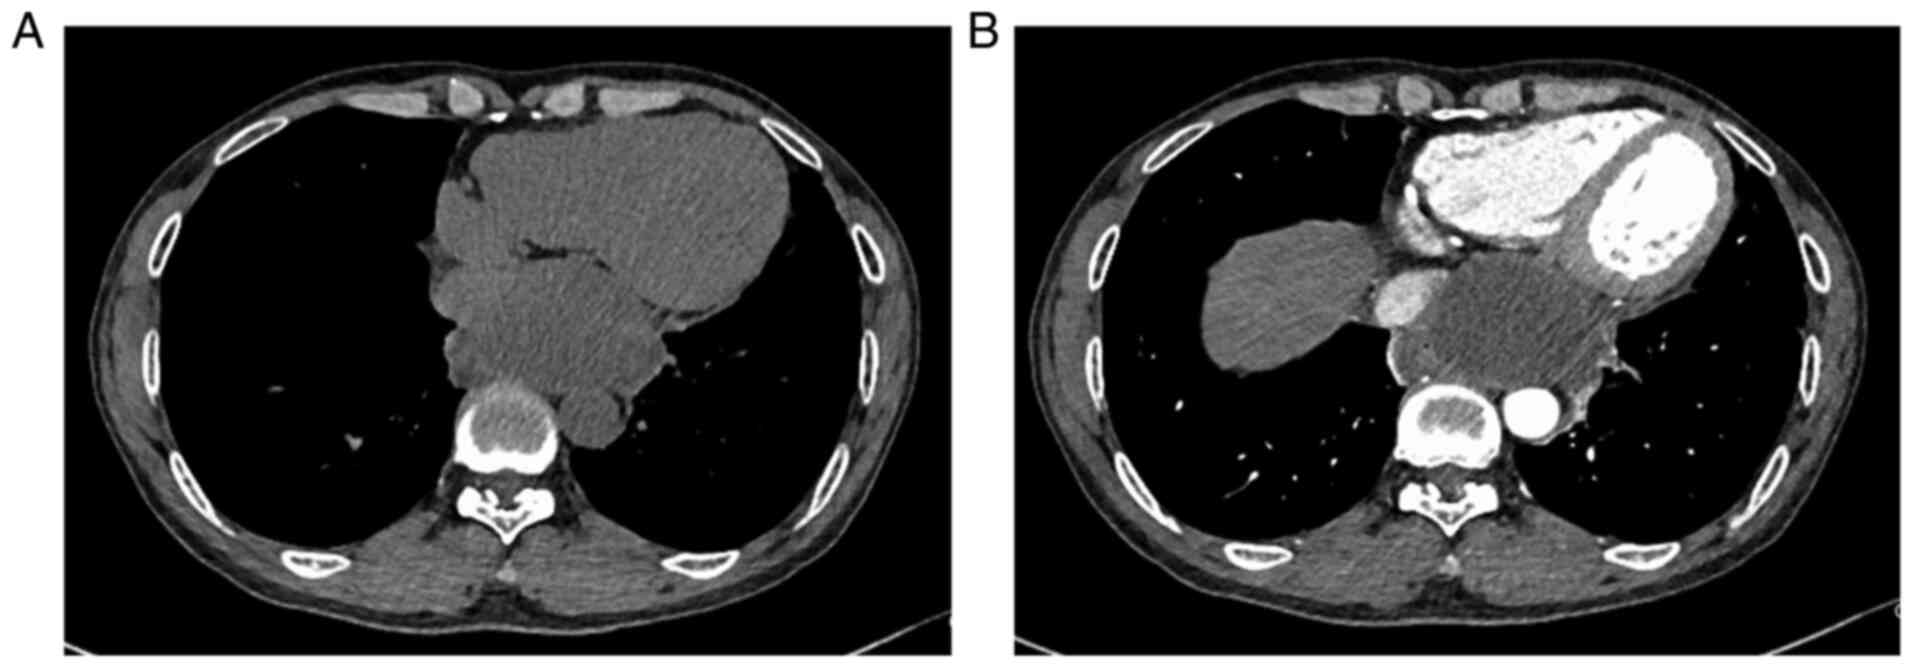

Since the patient had chest pain, the cardiologist

ordered color doppler echocardiography, coronary computed

tomography (CT) and enhanced chest CT to determine the cause. Color

echocardiography indicated a posterior left atrial cystic

hypoechoic mass and coronary CT displayed a cystic mass in the

posterior mediastinum. Plain and enhanced thoracic CT indicated a

cystic hypodense mass of ~7.7x4.7 cm above the esophageal hiatus in

the posterior mediastinum, with a thick wall, mild enhancement,

partly clear boundary, arc-shaped indentation adjacent to the

heart, esophagus and inferior vena cava, and the boundary between

the inner margin and esophagus was unclear, which revealed a

possible mediastinal cyst (Fig.

1). Plain and enhanced mediastinal magnetic resonance imaging